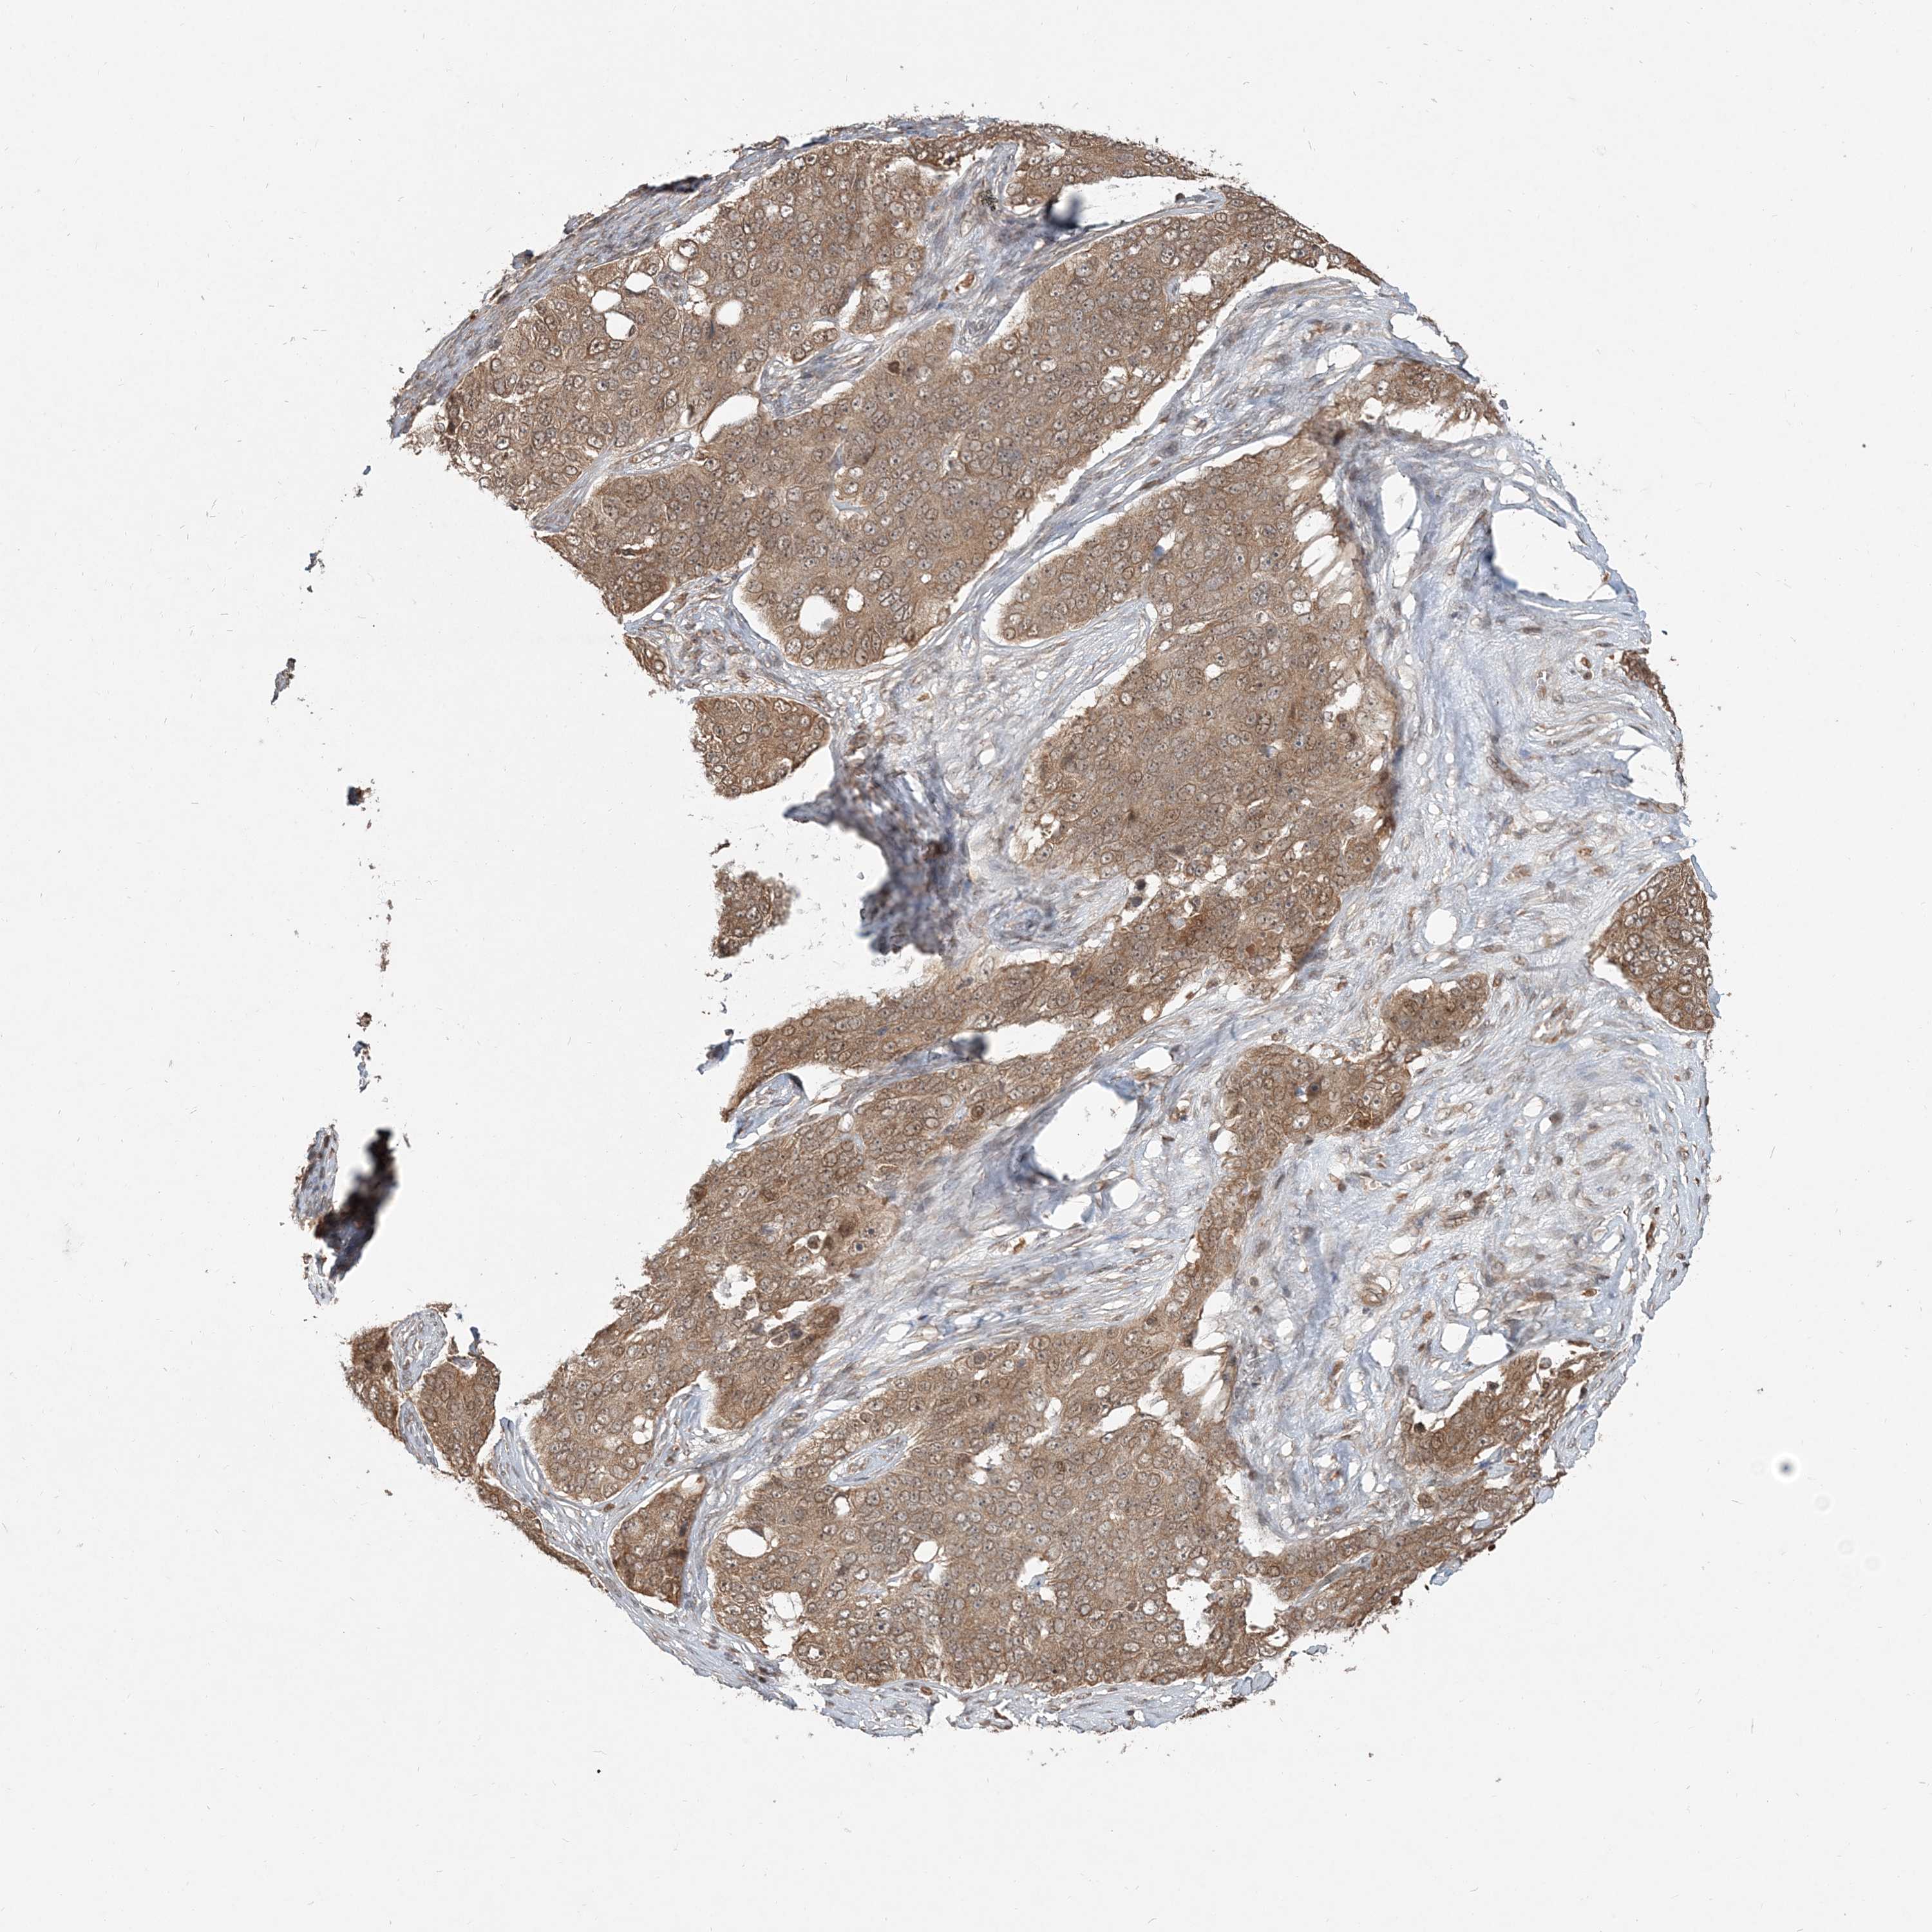

OVARIAN CANCER - Protein expressioni

A mouse-over function shows sample information and annotation data. Click on an image to view it in a full screen mode. Samples can be filtered based on level of antibody staining by selecting one or several of the following categories: high, medium, low and not detected. The assay and annotation is described here.

Note that samples used for immunohistochemistry by the Human Protein Atlas do not correspond to samples in the TCGA dataset.

Antibody stainingi

Antibody staining in the annotated cell types in the current human tissue is reported as not detected, low, medium, or high, based on conventional immunohistochemistry profiling in selected tissues. This score is based on the combination of the staining intensity and fraction of stained cells.

Each image is clickable and will lead to virtual microscopy that enables deeper exploration of all samples and also displays staining intensity scores, fraction scores and subcellular localization as well as patient and tissue information for each sample.

Antibody HPA076632

Antibody CAB037112

Staining

High

Medium

Low

Not detected

Intensity

Strong

Moderate

Weak

Negative

Quantity

>75%

75%-25%

<25%

None

Location

Nuclear

Cytoplasmic/membranous

Cytoplasmic/membranous,nuclear

Cystadenocarcinoma, serous, NOS

Cystadenocarcinoma, mucinous, NOS

Carcinoma, endometroid

Carcinoma, NOS